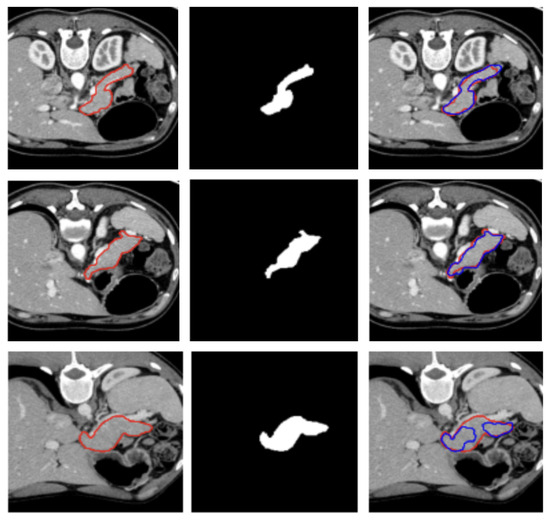

Machine learning, especially deep learning, has become prevalent in medical imaging analysis to assist in the detection, diagnosis, and treatment of various diseases. Despite the success of deep learning in medical imaging analysis, the main bottleneck in medical imaging analysis is the lack of large-sized and properly annotated datasets, which are very costly to establish. Recently, many studies have attempted to use various mathematical models to improve deep learning to address this challenge. In particular, semi-supervised, self-supervised, and unsupervised deep learning algorithms have showed promising results in medical imaging analyses, including image registration, detection, classification, and segmentation. Papers focused on using novel machine learning algorithms to solve problems in medical imaging analysis are welcome to be submitted to this Special Issue.